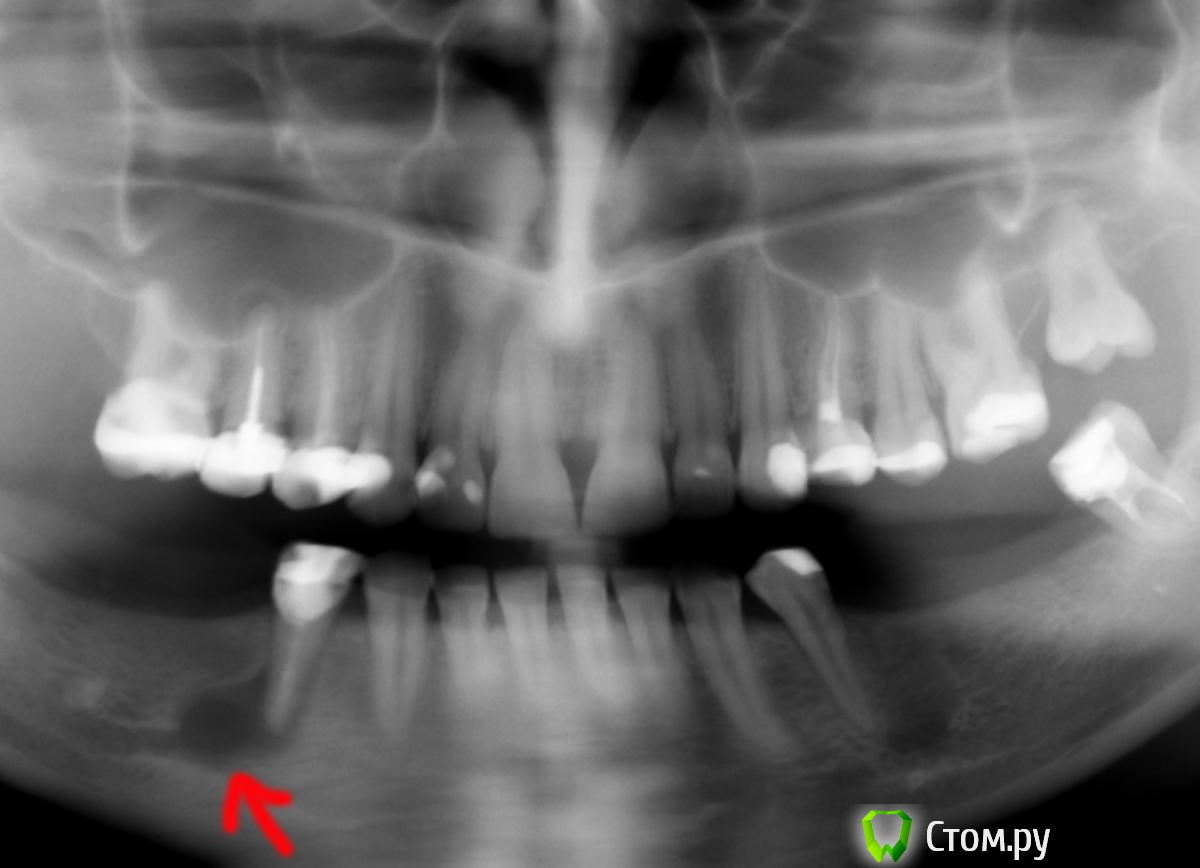

ЮлияС Опубликовано 11 августа, 2014 Поделиться Опубликовано 11 августа, 2014 (изменено) Здравствуйте.Была в нескольких поликлиниках. Везде говорят, что надо удалять зуб и ставить импланты. Ставить импланты возможности у меня нет .Возможно ли удалить кисту, сохранив этот зуб?Зуб не беспокоит. Языком чувствуется твёрдая шишка. Изменено 11 августа, 2014 пользователем ЮлияС Ссылка на комментарий